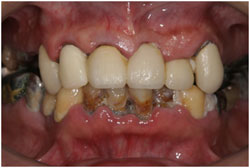

歯周病の症例1(抜かないための治療)

- <治療前>

- 重度歯周病です。